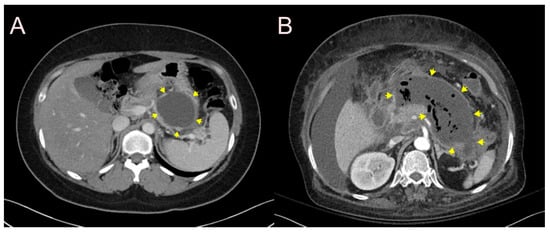

2.3. Stent for EUS-Guided Gallbladder (GB) Drainage

2.3.1. Use of the Plastic Stent

2.3.2. Use of the SEMS

2.3.3. Use of the LAMS